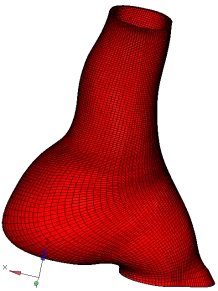

Abdominal Aortic Aneurysm (AAA) is an enlargement in the lower part of the main artery Aorta by 1.5 times its normal diameter. AAA can cause death if rupture occurs. Elective surgeries are recommended to prevent rupture based on geometrical measurements of AAA diameter and diameter growth rate. Reliability of these geometric parameters to predict the AAA rupture risk has been questioned, and biomechanical assessment has been proposed to distinguish between patients with high and low risk of rupture. Stress in aneurysm wall is the main variable of interest in such assessment. Most studies use finite element method to compute AAA stress. This requires discretising patient-specific geometry (aneurysm wall and intraluminal thrombus ILT) into finite elements/meshes. Tetrahedral elements are most commonly used as they can be generated in seemingly automated and effortless way. In practice, however, due to complex aneurysm geometry, the process tends to require time consuming mesh optimisation to ensure sufficiently high quality of tetrahedral elements. Furthermore, ensuring solution convergence requires large number of tetrahedral elements, which leads to long computation times. In this study, we focus on generation of hexahedral meshes as they are known to provide converged solution for smaller number of elements than tetrahedral meshes. Generation of hexahedral meshes for continua with complex/irregular geometry, such as aneurysms, requires analyst interaction. We propose a procedure for generating high quality patient-specific hexahedral discretisation of aneurysm wall using the algorithms available in commercial software package for mesh generation. For aneurysm cases, we demonstrate that the procedure facilitates patient-specific mesh generation within timeframe consistent with clinical workflow constraints while requiring only limited input from the analyst.